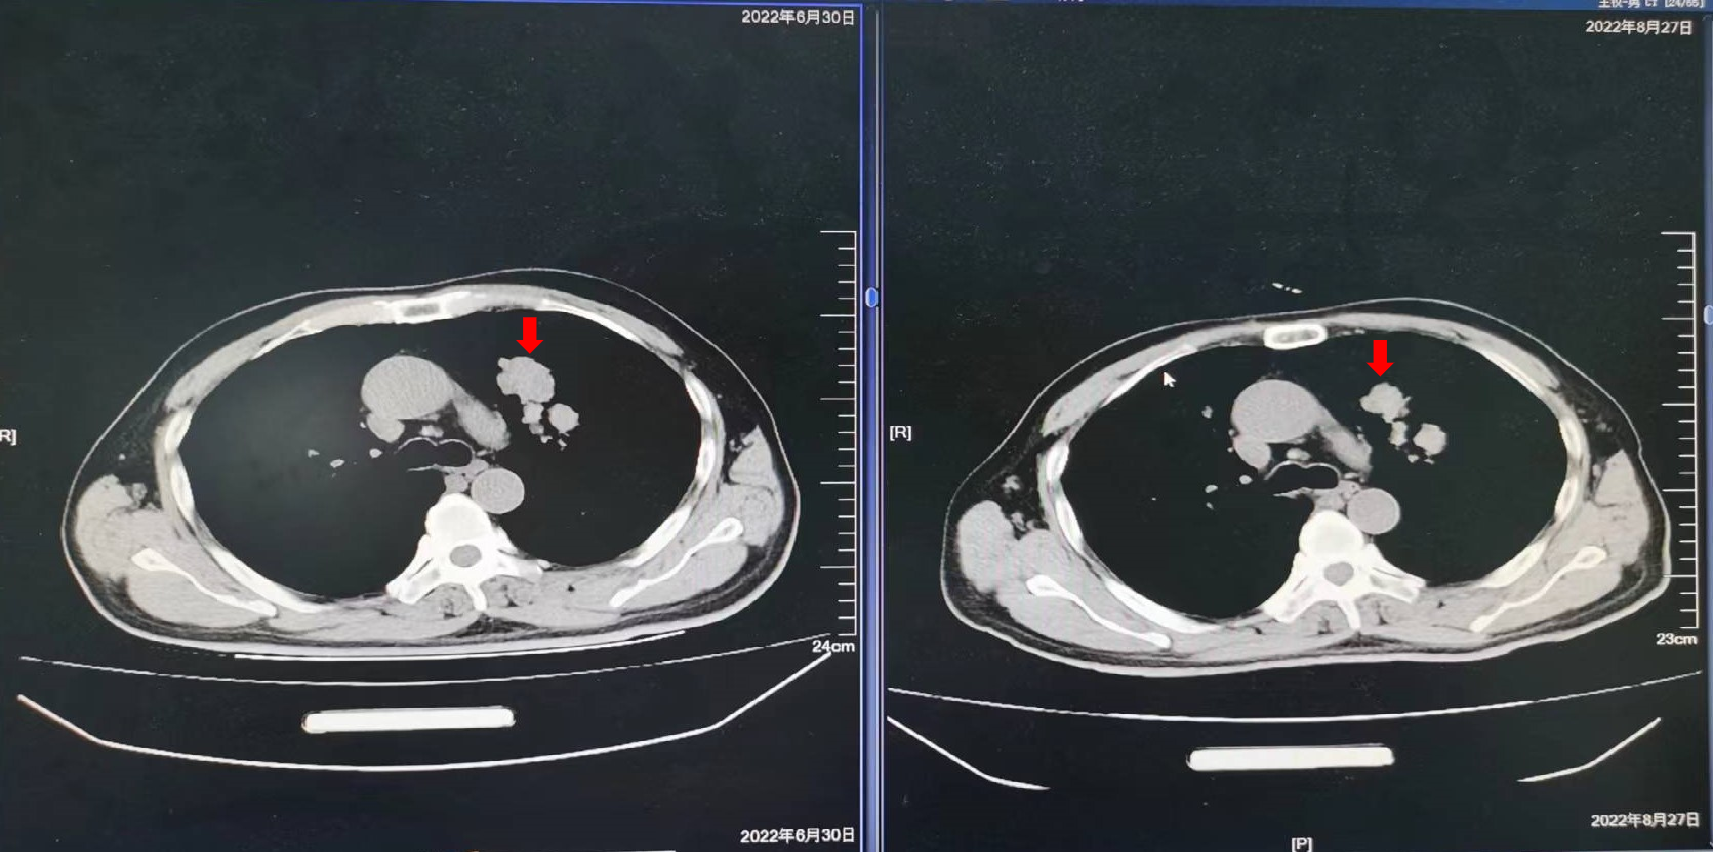

2019年10月16日:复查影像学检查提示新发肺转移,建议贝伐珠单抗,患者拒绝,继续XELOX方案化疗2周期,卡培他滨口服1周期,疗效为PD。

2021年5月27日:开始口服曲氟尿苷替匹嘧啶片(TAS-102)55mg每日2次 d1-5,d8-12,Q4W配合信迪利单抗免疫治疗。

疗效评价:SD,患者右腹股沟肿胀疼痛明显减轻,停用止痛药,PFS时间为10个月,主要不良反应为Ⅱ度骨髓抑制。